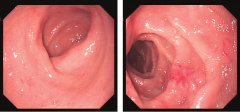

小腸炎是細(xì)菌、病毒、真菌和寄生蟲等引起的炎癥表現(xiàn)。臨床表現(xiàn)主要有腹痛、腹瀉、稀水便或黏液膿血便。部分病人可有發(fā)熱及里急后重感覺,按病程長(zhǎng)短不同,分為急性和慢性兩類。 病因...

1.病史 起病急,發(fā)病前多有不潔飲食史。受冷、勞累,腸道蛔蟲感染及營(yíng)養(yǎng)不良為誘發(fā)因素。 2.腹痛 起病急驟,突然出現(xiàn)腹痛,也??蔀樽钕劝Y狀,多在臍周。病初常表現(xiàn)為逐漸加劇的臍周或...